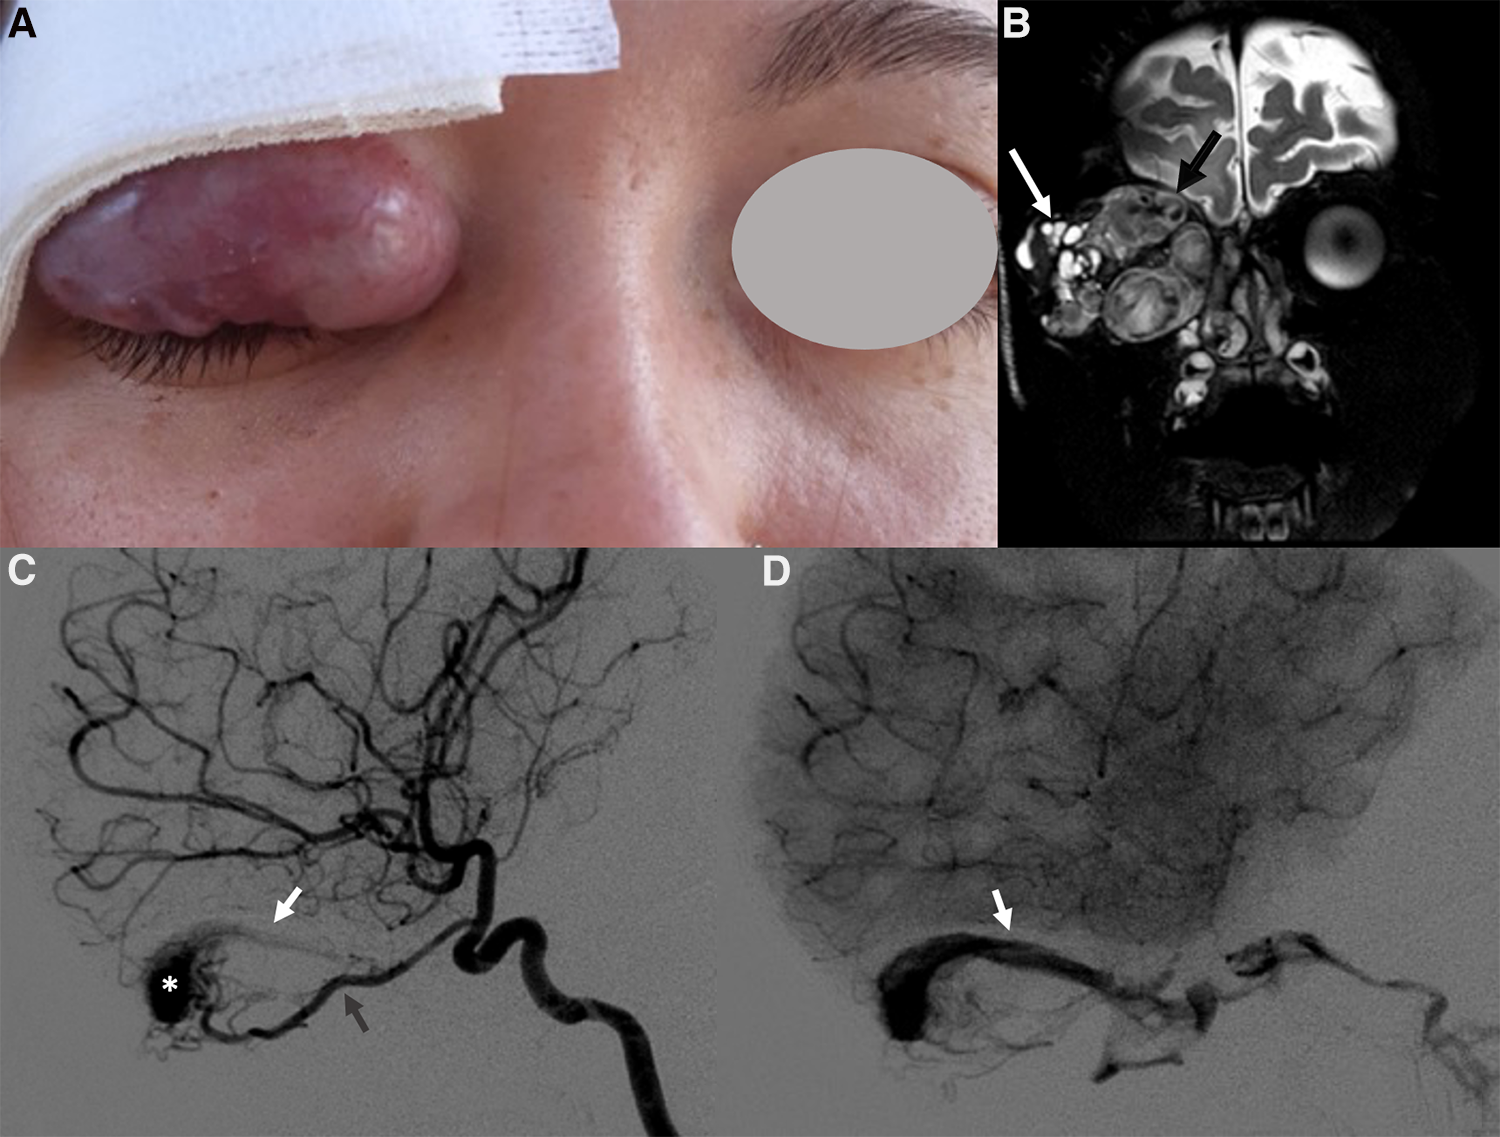

Noninvasive imaging is mandatory: it allows proper confirmation of diagnosis, sets a baseline for the patient and helps define the architecture of the malformation (68). The AVM has no parenchymal component and therefore it appears on gray-scale US as a poorly defined heterogeneous structure, usually surrounded by fat. At the color Doppler examination, the malformation is a high flow lesion: there are numerous vessels (“high vascular density”) with increased diastolic flow and arterialization of the draining vein. The spectral Doppler analysis shows arterial vessels with high-velocity flow and low resistive index (64). MRI and CT angiography are ideal noninvasive modalities for visualizing the entire course and extent of an AVM, to assess organ involvement and for planning endovascular or surgical management (13). MRI is the finest technique to estimate the expansion of the malformation and its rapports with adjacent structures (69). Dilated and tortuous vascular structures representing the hypertrophied feeding arteries and the draining veins are seen, appearing as prominent flow voids on spin-echo sequences, in the absence of a discrete enhancing soft tissue mass, thus aiding in the differential diagnosis with hemangiomas (Figure 11). In the very early cases, subtly hypertrophied vessels can be the only findings visible (Figure 11). In case of hemorrhage or thrombosis, foci of hypersignal on T1w images will be found (Figure 12). When small, the AVM usually involves a single compartment whereas in larger lesions or those that have been previously treated the nidus may be difficult to define as pronounced secondarily induced angiogenesis is present (56) or may be centered in more than one compartment. At MRA there is rapid enhancement of the tangle of vessels, with early enhancement of the draining veins (Figure 12). Intraosseous infiltration causes low marrow signal intensity on T1-weighted images (70). The introduction of time-resolved MRI sequences allowed to evaluate the hemodynamics of an AVM, giving the precise topography, mapped in time, of arterial feeders and venous drainage prior to DSA: the progressive opacification of the nidus and of the draining veins can be well-demonstrated and critical findings such as arterial or intranidal aneurysms or venous varices can be easily visualized (Figures 11, 12). In children, the identification or documentation of an AVM in the cerebro-facial region should prompt investigation for other clinically silent AVMs along the same metameric level due to possible syndromic associations (71). In case of suspected bone involvement or when the AVM is centered within the bone, CT and CTA may be the best imaging tools. Intraosseous AVMs present as osteolytic lesions with intense enhancement, as the lytic bony defects represent dilated intraosseous venous pouches or dilated draining veins (56). CT may also show complications such as bone thickening (or mature periosteal reaction), seen as a result of chronic venous hypertension, or osteolysis. DSA remains the most invaluable tool to confirm the diagnosis: it delineates the angioarchitecture and real-time hemodynamics of the AVMs with no venous contamination of the arterial phase, allowing also their endovascular treatment when necessary (Figures 11, 12).

Figure 12. Right orbital AVM in a 14-year-old girl with progressive proptosis, strabismus and visual loss. A red pulsatile mass in the upper lid was already evident at clinical examination (A); a thrill was also perceptible at palpation. Coronal T2 TSE sequence (B) shows a massive trans-spatial expansile lesion occupying the entire orbit, distorting its anatomy; signal intensity is highly inhomogeneous due to the presence of tortuous flow-voids (black arrow in B) and blood products of varying age (white arrow in B). The other MR sequences did not demonstrate any intracranial extension of the vascular malformation (not shown). The arterial phase of the DSA (lateral view, C) depicts the dilated and slightly tortuous right ophthalmic artery (grey arrowhead, arising from the supraclinoid segment of the internal carotid artery) feeding the orbital AVM, the nidus (white asterisk) and the early opacification of the draining vein, the superior ophthalmic vein (white arrowhead). The venous drainage is better seen in the venous phase of the DSA (lateral view, D), occurring mainly through the dilated right superior ophthalmic vein (white arrowhead), which drains into the cavernous sinus.